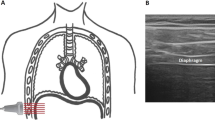

Excursion of the posterior part of the right hemidiaphragmatic dome was quantified using M-mode as described previously [9]. The transducer was placed below the right costal margin between the midclavicular and midaxillary line and tilted cranially, medially, and dorsally to achieve a perpendicular view of the posterior part of the hemidiaphragm. From this view, the hemidiaphragmatic exploration line was identified, and diaphragmatic excursion was recorded as a one-dimensional, downward-anterior movement using M-mode (Fig. 2A). The left hemidiaphragm was not assessed with this technique due to frequent artefacts caused by air in the stomach.

Ultrasonographic endpoint. A Excursion of the posterior part of the right hemidiaphragm performed between the midaxillary and midclavicular line. B Excursion of the hemidiaphragmatic top point in the midaxillary line. C Change in intrathoracic area of the hemidiaphragm performed in the midaxillary line. D Diaphragmatic thickness of the right hemidiaphragm

For assessment of the hemidiaphragmatic top point excursion, the transducer was placed in the midaxillary line to identify the right or left hemidiaphragm, respectively [10]. The transducer was angled vertically, so the diaphragmatic movement could be followed as a cranio-caudal movement (Fig. 2B). Subsequently, B-mode cine loops were stored for The Area Method (below).

The Area Method was performed by tracing the hemidiaphragmatic domes from inspiration to expiration, thus recording the excursion of the hemidiaphragm as a change in area [11]. Hence, diaphragmatic movement was isolated as the only change in intrathoracic area and the difference in intrathoracic area could be calculated by subtracting the area at inspiration from the area at expiration (Fig. 2C).

Measurement of diaphragmatic thickness was performed with the transducer placed perpendicularly to the diaphragmatic muscle layers in the midaxillary line 0.5–2 cm below the costodiaphragmatic recess to observe the diaphragm’s zone of apposition [12]. The diaphragm was identified as a 3-layered structure consisting of 2 hyperechogenic parts, the diaphragmatic pleura and peritoneum, with the hypoechogenic muscle layer in between. We assessed the diaphragmatic thickness from the inner layer of the diaphragmatic pleura to the inner layer of the diaphragmatic peritoneum at the end of inspiration (DTEI,) and the end of expiration (DTEE), and calculated the diaphragmatic thickening fraction (DTf) as: \({\text{DTf}}=\frac{{{\text{DT}}}_{{\text{EI}}}-{{\text{DT}}}_{{\text{EE}}}}{{{\text{DT}}}_{{\text{EE}}}}\) (Fig. 2D).